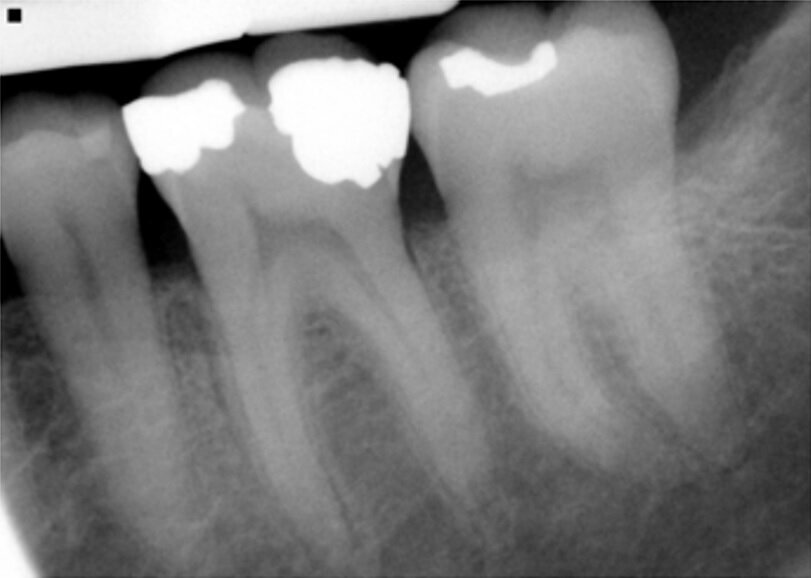

Fig. 14: Patient presented with complaint of pain on chewing on teeth 14 and 15 with increasing sensitivity to hot.

A 37-year-old male new patient presented with the complaint of pain with hot foods and beverages on teeth 14 (maxillary left first molar) and 15 (maxillary second molar) that had been increasing the past six months since he had restorations placed due to decay by the prior dentist before relocating to my area. A radiograph was taken, and slight apical widening was noted on both teeth (Fig. 14). Both teeth were responsive to testing with heat and cold that lingered for a minute or two after the stimulus was removed. Both teeth also tested to slight responsiveness to percussion stimuli. Patient was informed that based on what presented it was recommended that both teeth were moving toward needing endodontic treatment or we could adjust the occlusion and see if that helped with symptom improvement. The patient indicated due to the increasing sensitivity to hot foods and beverages he would prefer to initiate endodontic treatment at this time.